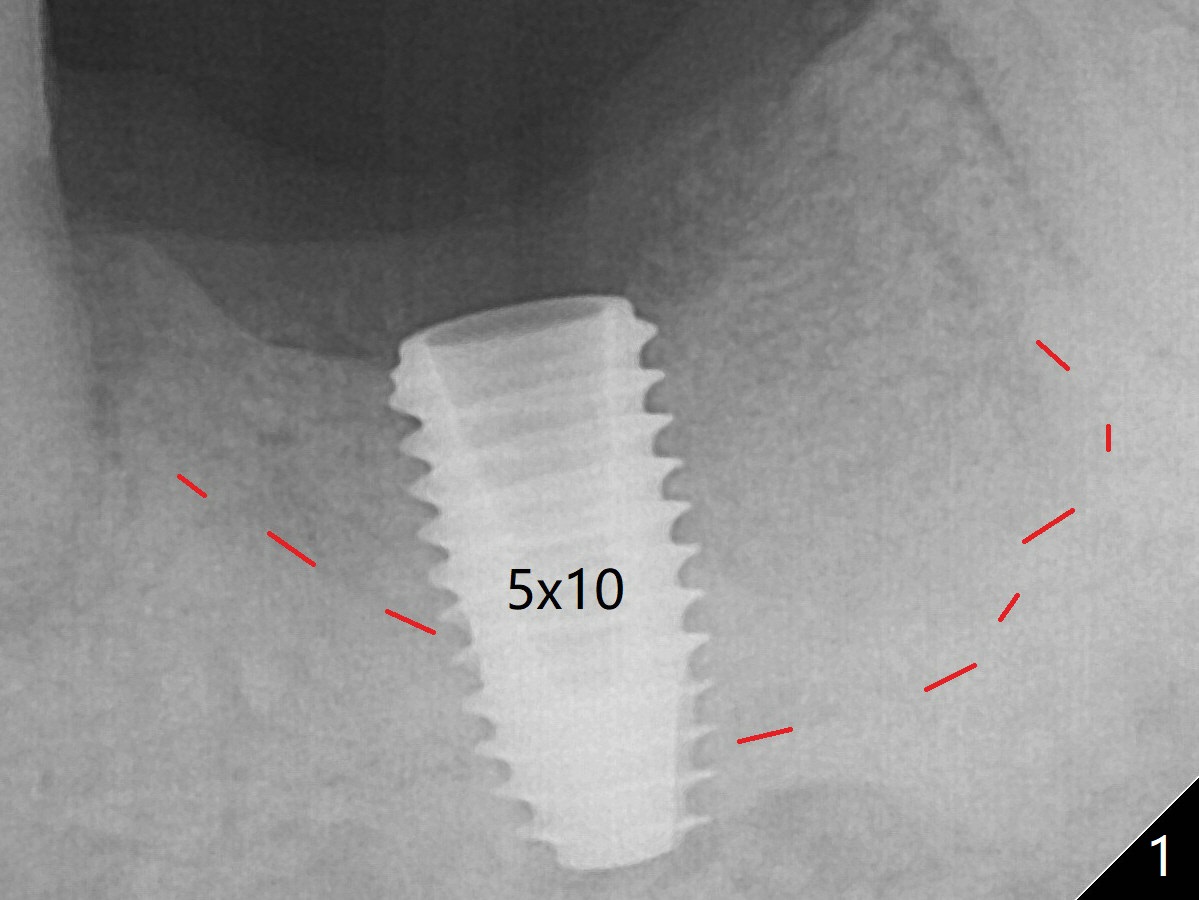

Osteotomy shows two layers of bone.  The first one feels slightly less dense than the normal bone (Fig.1 above the red dashed line), while the second one is extremely hard (3-4 mm in depth).  For the last 1.5 mm of the osteotomy, the 4.5 mm drill has to be withdrawn for bone shaving removal before finishing the osteotomy.  In all the graft bone contributes to implant stability (insertion torque > 50 Ncm).  At least the implant is surrounded by the bone with less likelihood of developing periimplantitis.  In fact the patient returns for impression 3 months 23 days postop; there is no bone loss at the crestal level (Fig.3).